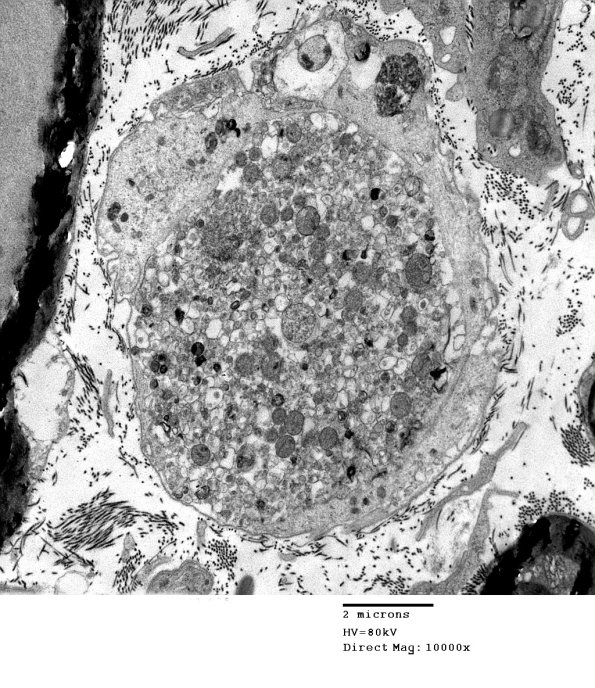

Some unmyelinated axons show impressive dilatation due to the accumulation of subcellular organelles including mitochondria, endoplasmic reticulum and autophagosomes.